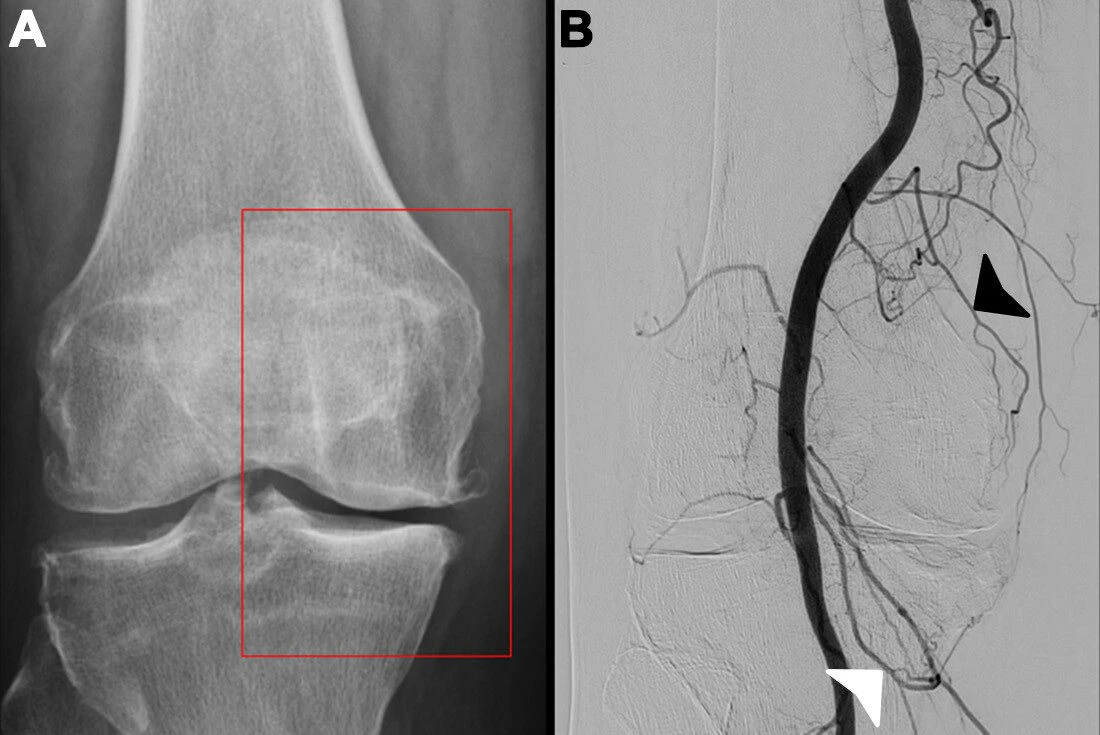

Genicular artery embolization (GAE) has proven safe and effective in a sizeable, real-world group of patients with pain and disability due to knee osteoarthritis, according to research published July 22 in Radiology.

To further validate the procedure, the group gathered data on patients who underwent the procedure at their center between December 2022 and July 2024. Patients had Kellgren-Lawrence grades of 2, 3, and 4 (severe) and all experienced knee pain for more than six months despite undergoing intra-articular injections of corticosteroids, hyaluronic acid, or platelet-rich plasma.